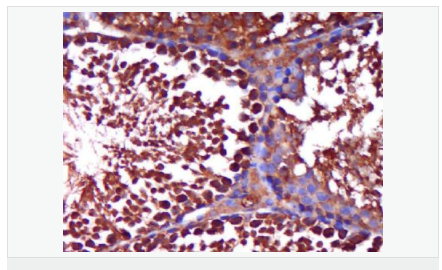

產(chǎn)品應用WB=1:500-2000 ELISA=1:5000-10000 IHC-P=1:100-500 IHC-F=1:100-500 Flow-Cyt=1ug/Test IF=1:100-500 (石蠟切片需做抗原修復)

AR是一個由917個氨基酸組成的蛋白質(zhì),位于雄激素靶組織細胞中或細胞表面上的特異分子部位或結構。 AR在前列腺癌中起著重要的作用,研究表明AR的表達與組織分型形成一定的相關性 ,AR在高分化的腫瘤中表達較多,而在低分化的腫瘤中表達較少。用于前列腺癌的檢測,指導臨床治療,目前可用于乳腺癌、食道癌等各項腫瘤的研究。